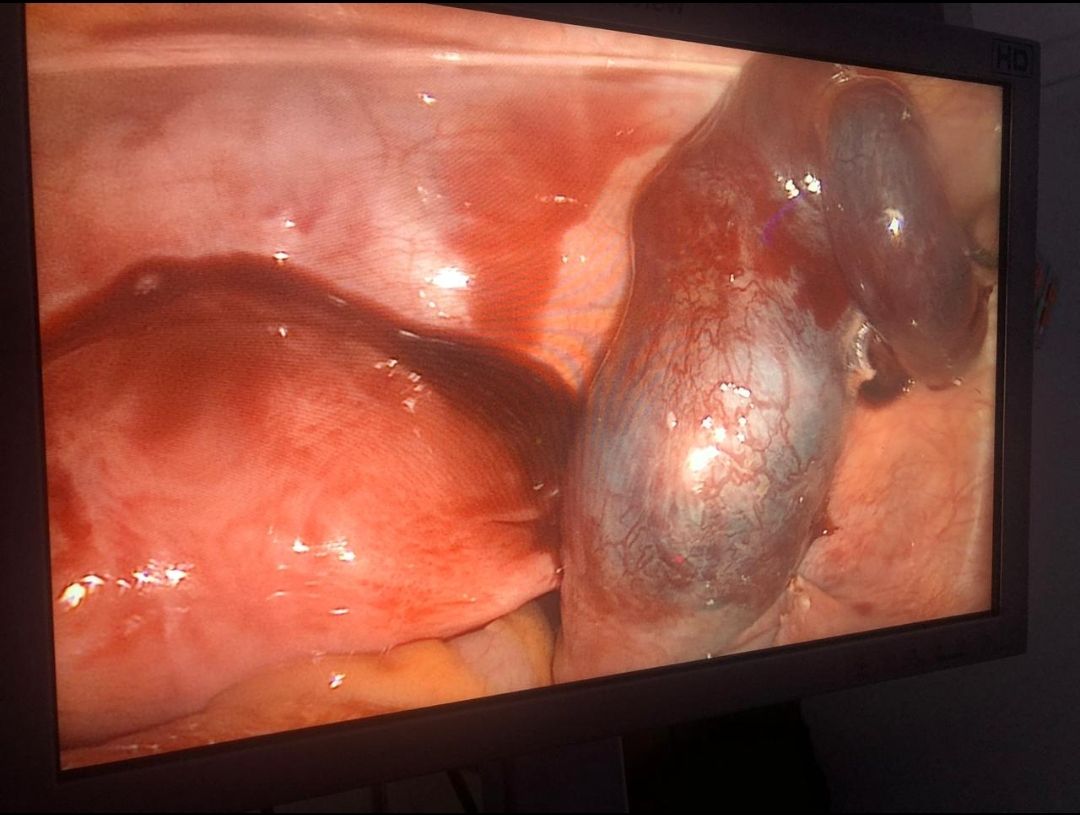

Tambien estoy ampliamente entrenado para cirugias para mejorar la fertilidad como la reseccion de miomas uterinos desde pequeños hasta muy grandes con conservación del útero (matriz), la eliminación de quistes ovaricos, tratamiento de endometriosis, y todo esto tanto por cirugia abierta como por laparoscopia (cirugia con camaras que permite una minima invasión y una rapida recuperación). Soy de los pocos expertos en México en correcciones mayores de deformidades uterinas (malformaciones müllerianas).

En la parte no relacionada con infertilidad tengo experiencia en Cesareas de alto riesgo, histerectomias abiertas y laparoscopicas, cirugias ovaricas, manejo del embarazo ectópico, entre otras.